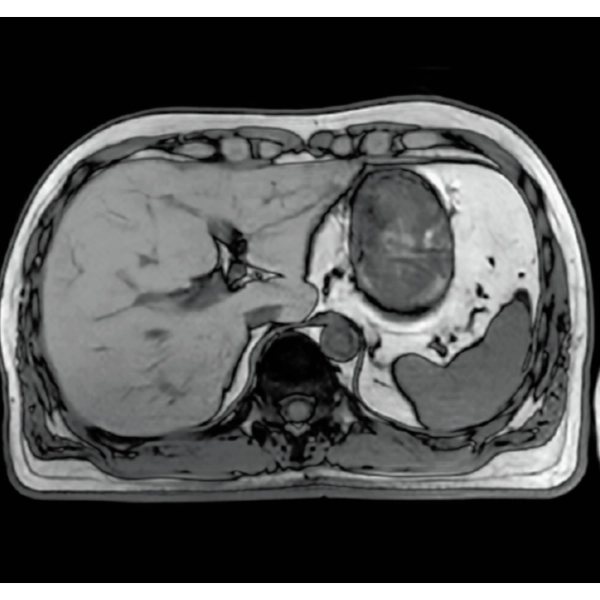

When motion artifacts occurs in the image due to coughing, sneezing, or involuntary movements, either or both the visual information acquired by monitoring cameras, Synergy Vision, and the intrabody information acquired by the navigator pulse can be used to provide an image with reduced artifacts. This reduces the re-imaging rate.

Body movements that affect image quality are detected from monitoring cameras based on thresholds derived for each body part.

Movements within the body are detected by navigator pulses. Body movements that significantly affect image quality are detected based on the error between pulses.